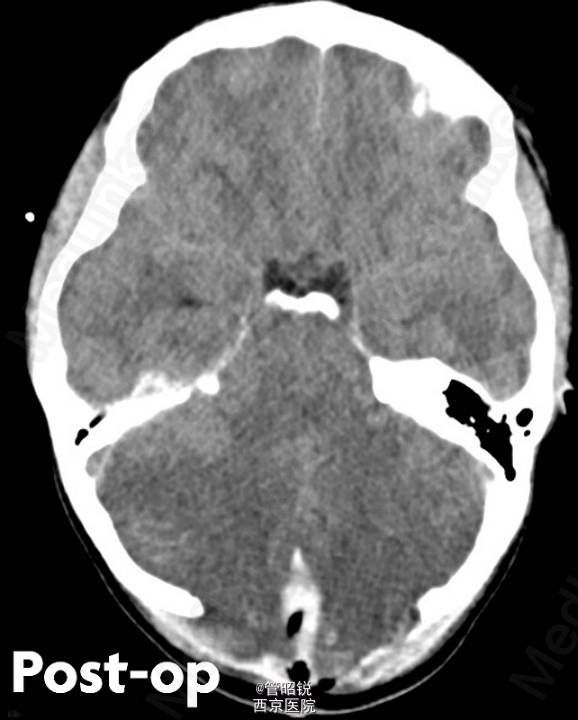

患者,男,29岁,头痛、颈痛2周 入院时CT正常,24小时后 T2WI (B) 和 T2W-FLAIR (C)显示高信号增强,脑水肿,沟回消失。CE-T1WI (D)显示脑膜线样增强。随后12小时的非增强CT显示小脑水肿压迫脑干,由于阻塞性脑积水使颞角膨大,需要紧急行颅后窝颅骨切除减压术。(影像资料比较典型。和大家分享下 AJNR-case of the week)

诊断:急性小脑炎 治疗上应早期应用激素治疗,水肿严重时应手术行颅骨减压。